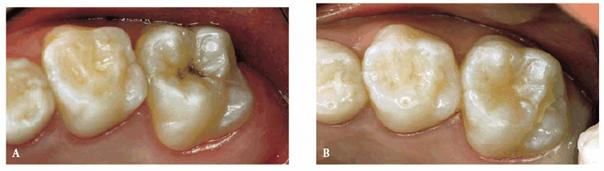

A male patient, 7 years, 2 months old.

PROBLEM: The patient was a high-caries-risk subject with poor oral

hygiene and an enamel-only lesion of tooth 3.

TREATMENT: Preventive resin restoration. After local anesthesia and

rubber dam isolation, a small high-speed diamond burr was applied to the

questionable fissure. It was essential to have adequate access to the

underlying dentin to be certain of complete caries removal. A glass ionomer

liner was placed over the dentin, extended to the amelodentinal junction, and

light-cured. An etching gel was placed on the enamel margins and on the

occlusal surface, washed, and dried. The bonding resin and the composite resin

were placed and polymerized, and, finally, a fissure sealant was placed over

the restoration and cured. After the rubber dam was removed, the occlusion was

checked (Figures 27-8A and B).

Figure 27-8A and B: An enamel caries is treated with a preventive resin restoration.

RESULT: The durability of preventive resin restoration has been proved

to be as good as amalgam, with less removal of sound tooth tissue and with

better esthetics.